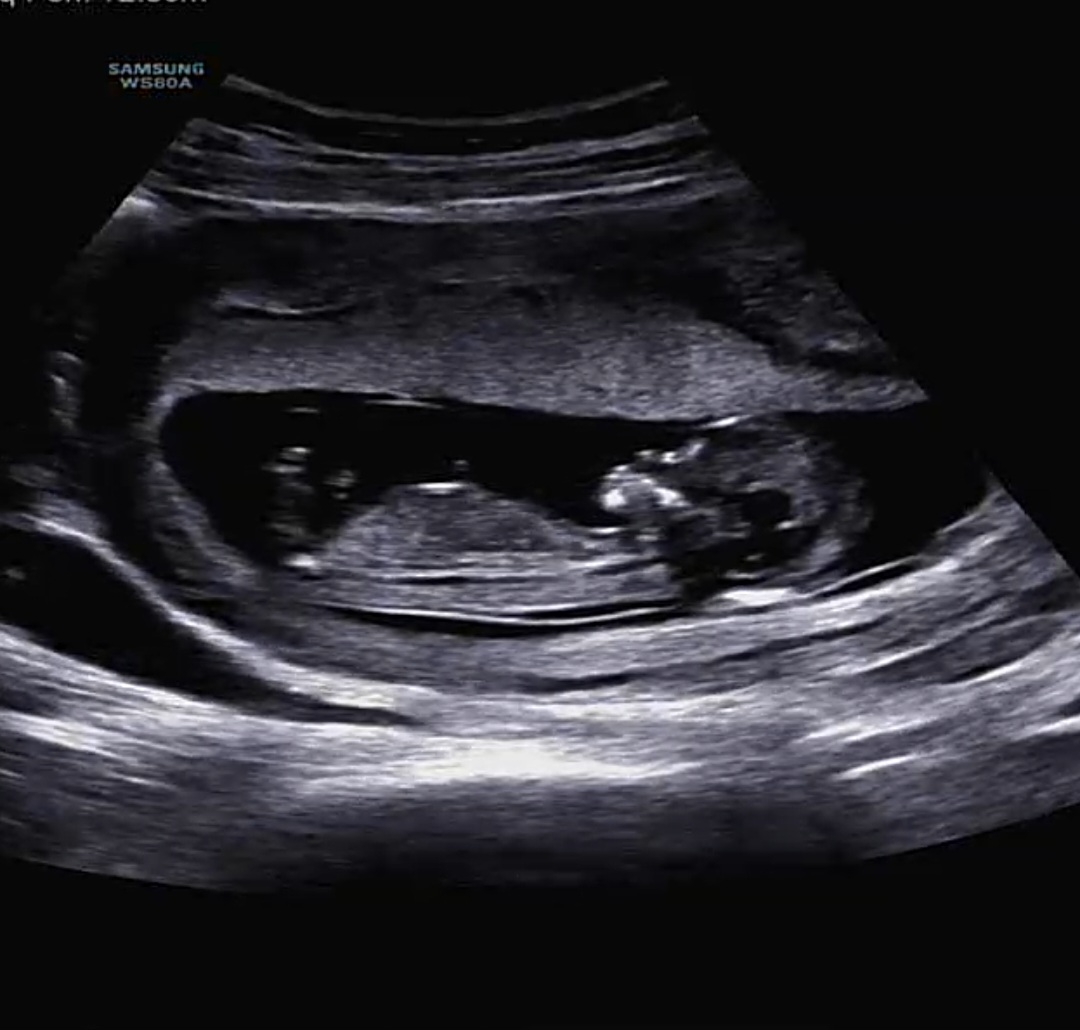

12주 2일차 1차 초음파 보고왔어요 잘크고있고 모두 정상이라서 기쁘네요ㅎㅎ 각도법? 잘보시는분 한번 봐주시면 감사합니다